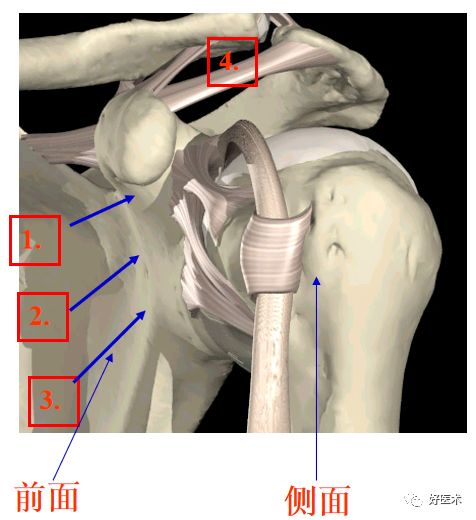

前方的韧带

1. 盂肱上韧带

2.盂肱中韧带

3.盂肱下韧带

4. 喙肩韧带

盂唇和盂肱韧带

1.盂唇

2. 盂肱上韧带

3. 盂肱中韧带

4.盂肱下韧带